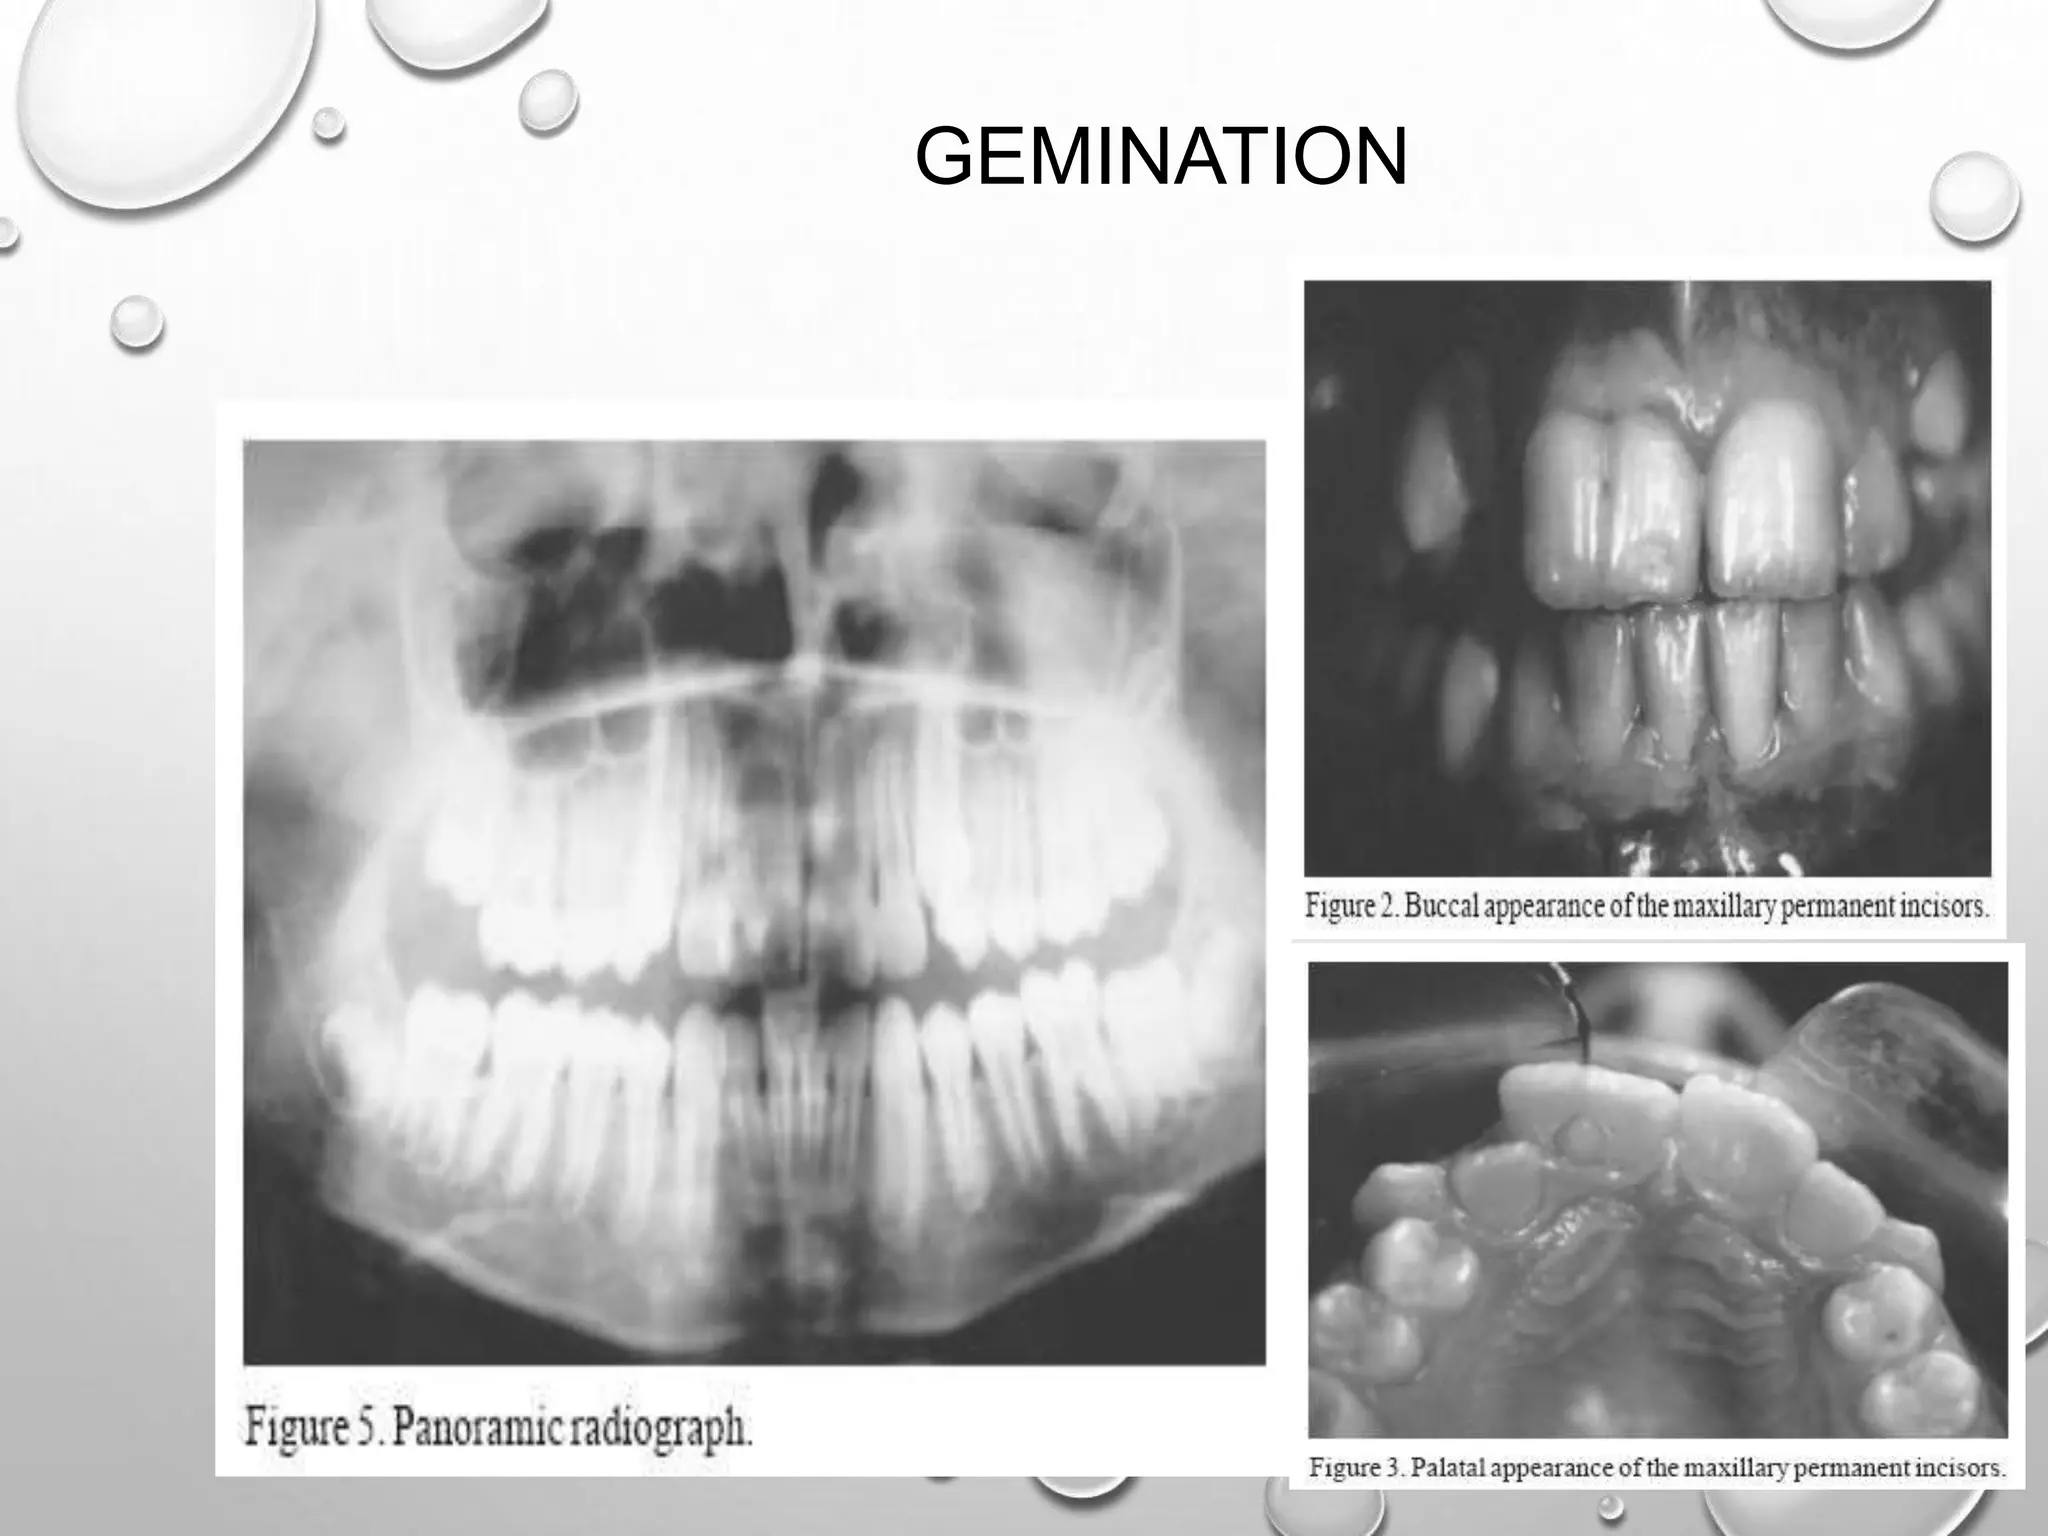

GEMINATION